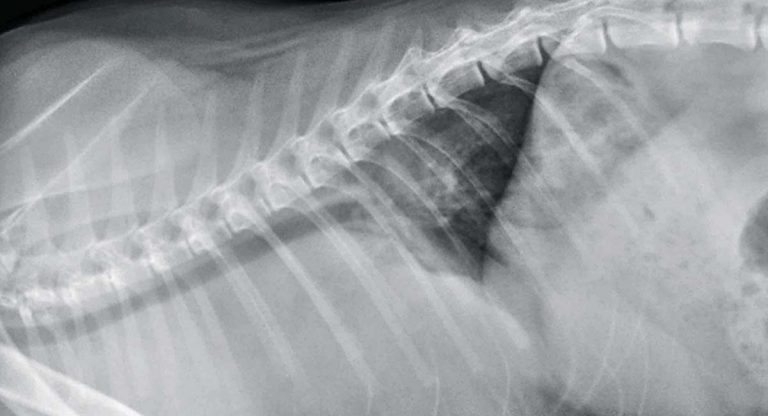

Figure 1. Thoracic radiograph, lateral view.

Mild rotation exists of the spine in both projections and the forelimb triceps musculature is partially superimposed over the cranial thorax on the lateral view. Wet coat artifact is also evident on dorsoventral projection. Both radiographs reveal a marked increase in soft tissue opacity predominantly within the cranial aspect of the thorax resulting in border effacement of the cranial cardiac silhouette.

Notably, on the dorsoventral projection, evidence exists of marked widening of the cranial mediastinum. On both views, only the caudal margin of the heart is visible and indicates the heart is displaced caudally, and to the right of midline within the thorax.

The size of the heart cannot be accurately assessed from these radiographs. There is evidence of elevation of the entire intrathoracic trachea and the tracheal carina has been displaced caudally from its normal position around the fifth intercostal space, to the seventh intercostal space.

On the dorsoventral projection there is also the impression of increased soft tissue opacity cranial to each scapulohumeral joint, most likely due to marked enlargement of the prescapular lymph nodes. Skeletal structures are within normal limits.

In summary, the key radiographic findings are marked widening of the cranial mediastinum and caudal and dorsal displacement of the trachea. Although tracheal elevation may be caused by a large cranial mediastinal mass, large volume of pleural fluid or heart base mass, only a cranial mediastinal mass would explain caudal displacement of the tracheal carina.